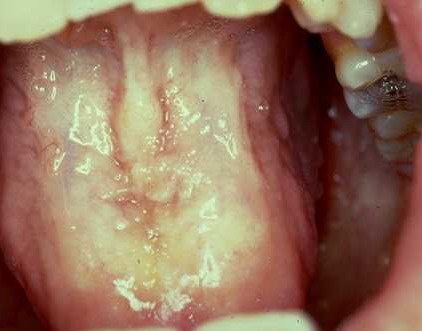

Hyalinosis Cutis et Mucosae=تنكس هياليني جلدي ومخاطي